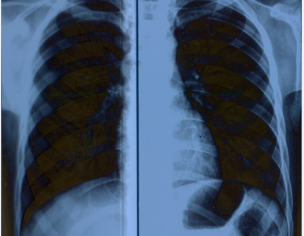

My son ribs bone structure is de-shaping. It's Pectus Carinatum case. Sheikh Zayed Dr. asked to use maximum milk and calcium products in May,2019 but issue is not getting resolved. Kindly advise.

there is possibility that your son is suffering from Rickets or some metabollic deficiency, his clinical examination may reveal some other findings as wel

because such deficiencies can leave some life lasting problems like bowing of bones or deformities

we have to check for ribs and spinal joints. please bring him to us for detailed evaluation and possible treatment